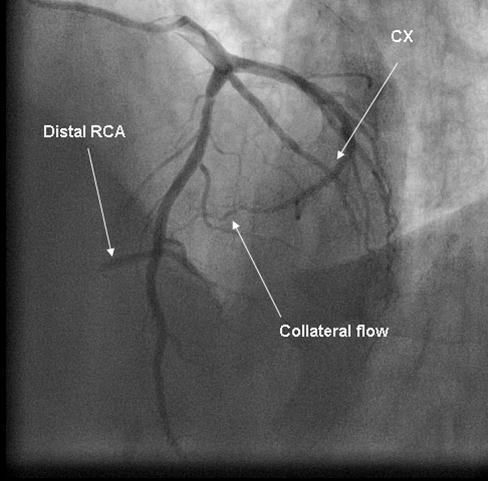

Coronary angiography was again performed. On injections into the left system, collaterals to the distal RCA were demonstrated (figure 1), arising from the left circumflex coronary artery (CX). Injections into the RCA demonstrated tight in-stent restenosis, (figure 2) and a drug eluting stent was successfully implanted. After the angioplasty, injections into the RCA were seen to retrogradely fill the CX (figure 3). The suspicion arose that maybe the left coronary artery had been inadvertently damaged during angiography, so the left coronary was again cannulated and injections performed, demonstrating entirely normal left main and CX arteries. However, the collateral flow that had previously been demonstrated from the CX to the RCA was no longer apparent. On review of the previous angiogram, it was noted that the RCA retrogradely filled the CX despite the original significant stenosis (figure 4). In essence, it became apparent that the bidirectional filling of the RCA from the CX and vice versa was in fact a direct continuity between the vessels and not collaterals, as free flow was noted from the RCA to the CX even when both arteries were completely patent.

Figure 1.Collateral flow from circumflex artery (CX) to right coronary artery (RCA) in cranial left anterior oblique view.

Collateral flow from circumflex artery (CX) to right coronary artery (RCA) in cranial left anterior oblique view.